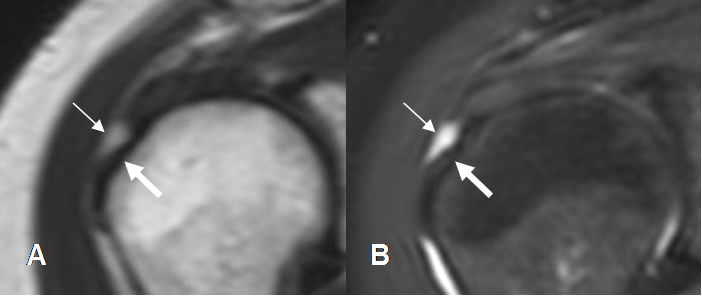

Fig 119. Ruptura parcial del supraespinoso.

A, B y C: RM coronal en T2. Diferentes grados de ruptura parcial del supraespinoso.

En A menor de 3 mm, B entre 3 y 6 mm y C, mayor de 6 mm.